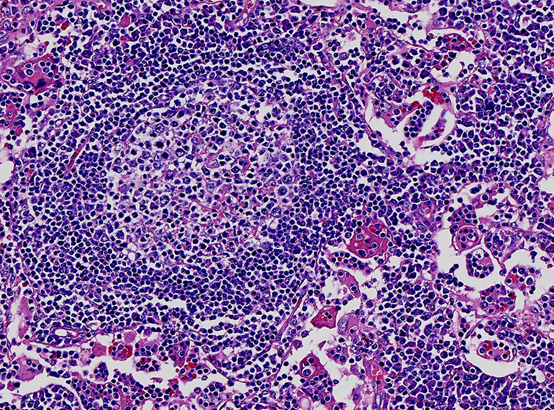

人体淋巴增生是多么的“绚丽多彩”

而事实上,它不过只是一个“淋巴组织增生”,本质上是一种慢性发炎,属于不治疗自己就可以好的小毛病。